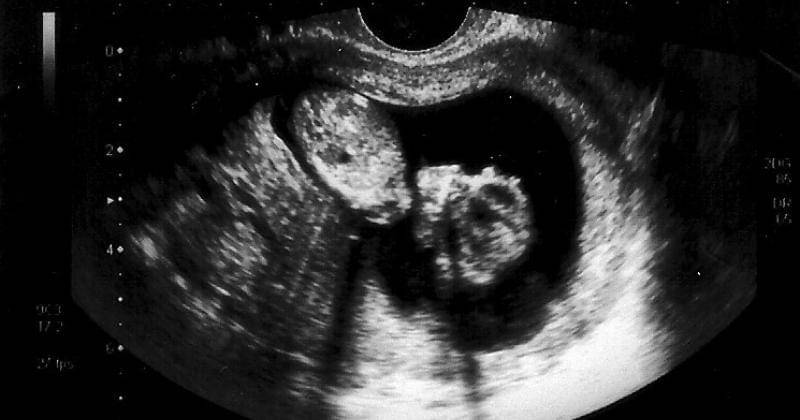

1. Ukuran janin dua bulan

Saat memasuki usia kehamilan dua bulan, ukuran janin yang ada di dalam rahim berukuran sebesar buah raspberry.

Dilansir dari What to Expect, panjang janin saat usia delapan minggu yaitu sekitar 1/2 hingga 3/4 inch atau setara dengan 1,2 centimeter - 1,9 centimeter. Sementara untuk beratnya sekitar satu gram.

3. Detak jantung sudah mulai jelas

Tidak hanya anggota tubuh yang sudah mulai terbentuk, namun detak jantung janin pada usia kehamilan dua bulan sudah mulai semakin jelas.

Di mana jantung berdenyut dengan kecepatan sebanyak 150 hingga 170 kali per menit. Jumlah ini dua kali lipat lebih cepat daripada detak jantung dewasa.

4. Janin sudah mulai bergerak

Dilansir dari What to Expect, memasuki dua bulan janin sudah mulai bergerak meskipun ibu hamil belum dapat merasakannya. Batang kecil si Kecil dan tunas anggota badan sudah mulai membuat gerakan spontan.